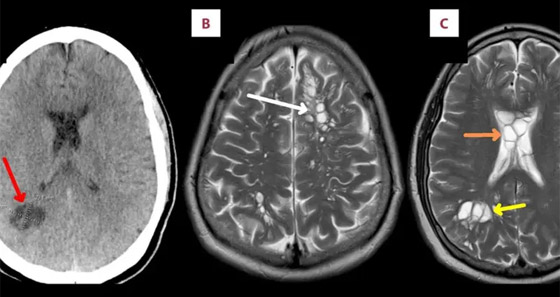

وأوضح الأطباء أن ما حدث كان بسبب تناول الرجل لحم الخنزير المقدد غير المطبوخ جيدًا، وفقا لما ذكرت شبكة بريطانية، حيث كشف تصوير بالأشعة المقطعية أجراه أطباء لدماغ الرجل، عن بيوض الدودة الشريطية، كما تم تشخيص المريض بداء الكيسات المذنَّبة العصبي.

يشار إلى أن هذا الداء يعدّ نوعاً خاصاً من داء الكيسات المذنبة، ويحدث بسبب عدوى بالشريطية الوحيدة، وهي شريطية حقيقية (Eucestoda) تُوجد في الخنازير، والتي يمكن أن تصل إلى الأنسجة مثل العضلات والدماغ. في حين نفى المريض تناول طعام نيء أو وجبات من الشارع، إلا أنه اعترف بعادة تناول لحم الخنزير المقدد المطبوخ بشكل خفيف وغير المقرمش معظم حياته. في حين أكد الباحثون أن الرجل تعرض للعدوى الذاتية، بعد عدم غسل اليدين بشكل لائق.